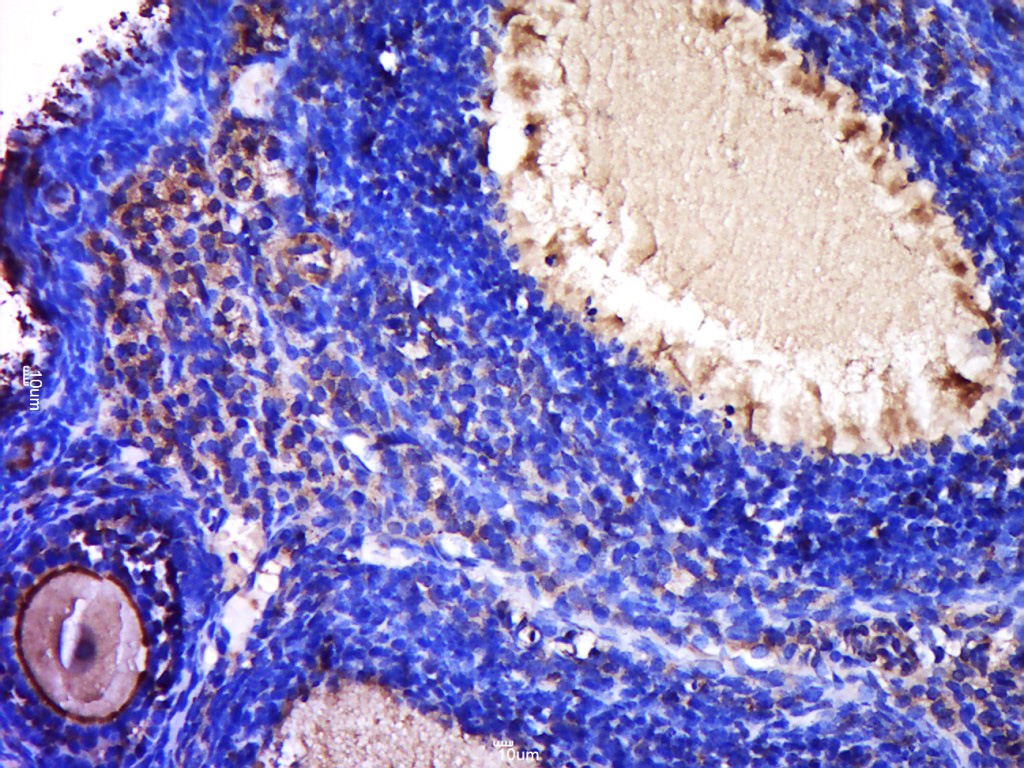

Paraformaldehyde-fixed, paraffin embedded (Mouse placenta); Antigen retrieval by boiling in sodium citrate buffer (pH6.0) for 15min; Block endogenous peroxidase by 3% hydrogen peroxide for 20 minutes; Blocking buffer (normal goat serum) at 37°C for 30min; Antibody incubation with (Processed zona pellucida sperm-binding protein 2; ZP2) Polyclonal Antibody, Unconjugated (bs-20812R) at 1:400 overnight at 4°C, followed by a conjugated secondary (sp-0023) for 20 minutes and DAB staining.

Paraformaldehyde-fixed, paraffin embedded (Rat ovary); Antigen retrieval by boiling in sodium citrate buffer (pH6.0) for 15min; Block endogenous peroxidase by 3% hydrogen peroxide for 20 minutes; Blocking buffer (normal goat serum) at 37°C for 30min; Antibody incubation with (Processed zona pellucida sperm-binding protein 2; ZP2) Polyclonal Antibody, Unconjugated (bs-20812R) at 1:400 overnight at 4°C, followed by a conjugated secondary (sp-0023) for 20 minutes and DAB staining.